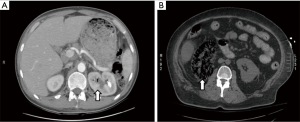

Laboratory data are summarized in Table 2. Median WBC count was 13. The median baseline creatinine was 1.1 and median creatinine increase during hospitalization was 0.5. Microbiology information is summarized in Table 3. Nine patients (64%) had a positive urine culture from a single organism; the remainder had mixed urine cultures. E-coli was the most common organism identified (50%) followed by Klebsiella (21%) and Candida (14%). The most common class of antibiotic therapy was fluoroquinolones (36%) followed by 3rd generation cephalosporins (29%) and extended spectrum penicillin (14%). Antibiotic coverage was changed at least twice in 50% of the patients. Seven patients (50%) were managed with antibiotic therapy alone (Table 4). Five patients (36%) required percutaneous drainage, and of these patients, two patients required placement of a second percutaneous nephrostomy tube due to incomplete drainage with the initial percutaneous drain. Only one patient required an interval nephrectomy. No patients required immediate nephrectomy. There were no deaths in our cohort. When the outcomes of patients with stones (Figure 1A) were compared to outcomes of patients without stones (Figure 1B), emphysematous pyelonephritis with gas confined to the collecting system (Huang class 1) was significantly more common in patients with stones than in patients without stones (P=0.03) (Table 5).

Comorbid conditions and presenting symptoms most commonly associated with emphysematous pyelonephritis are similar to those reported in other series with a few exceptions (11). Our series reports a much lower associated rate of diabetes mellitus (57%)—most large series report rates of >90% (5). Our associated rate of urolithiasis (57%) was higher than reported in the literature (22%) (2). When patients without stones and those with stones were compared, it was noted that those with stones had significantly lower classification of disease based on initial imaging. Patients with stones tended to be younger than those without stones and had less of an increase in creatinine during their hospitalization. Emphysematous pyelonephritis associated with urolithiasis is likely the result of bacterial activity in or associated with the stones rather than within the renal parenchyma, leading to a less aggressive form of the disease.